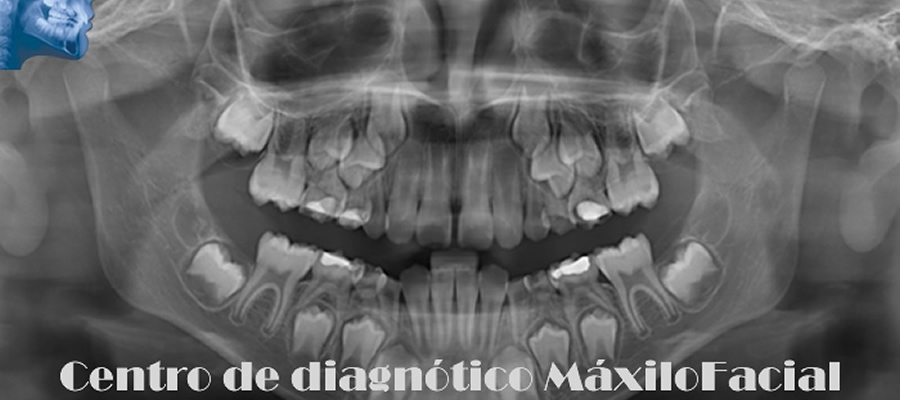

Radiografía Panorámica Dental

Permite obtener una apreciación global de los maxilares, a través de ella podemos detectar caries, enfermedad de las encías, quistes, tumores, fracturas, etc. Muchas de estas patologías son detectadas de forma casual, lo que la convierte en un estudio de protocolo a la hora de iniciar un tratamiento odontológico.

A continuación queremos mostrarle nuestra galería con algunas imágenes de casos llegados a Cedimax - Centro de Diagnóstico Maxilofacial, si requiriera más ejemplos de casos no dude en contactarse con nosotros.